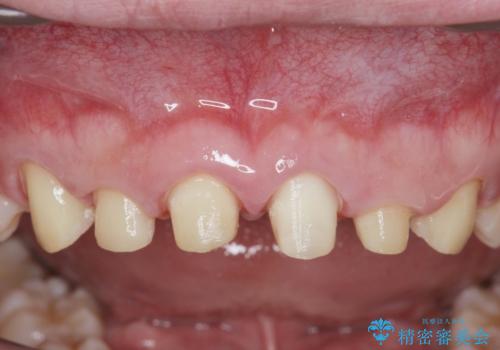

ただ、白いオールセラミッククラウンを製作・装着するのではなく、将来にわたり安定した状況を獲得するため、歯周外科を行い歯ぐきと周囲の歯槽骨の形態を整えていきます。

歯周外科を行ったことで、歯ぐきの形態や腫れが改善され、審美性だけでなく清掃性も大きく改善することができました。